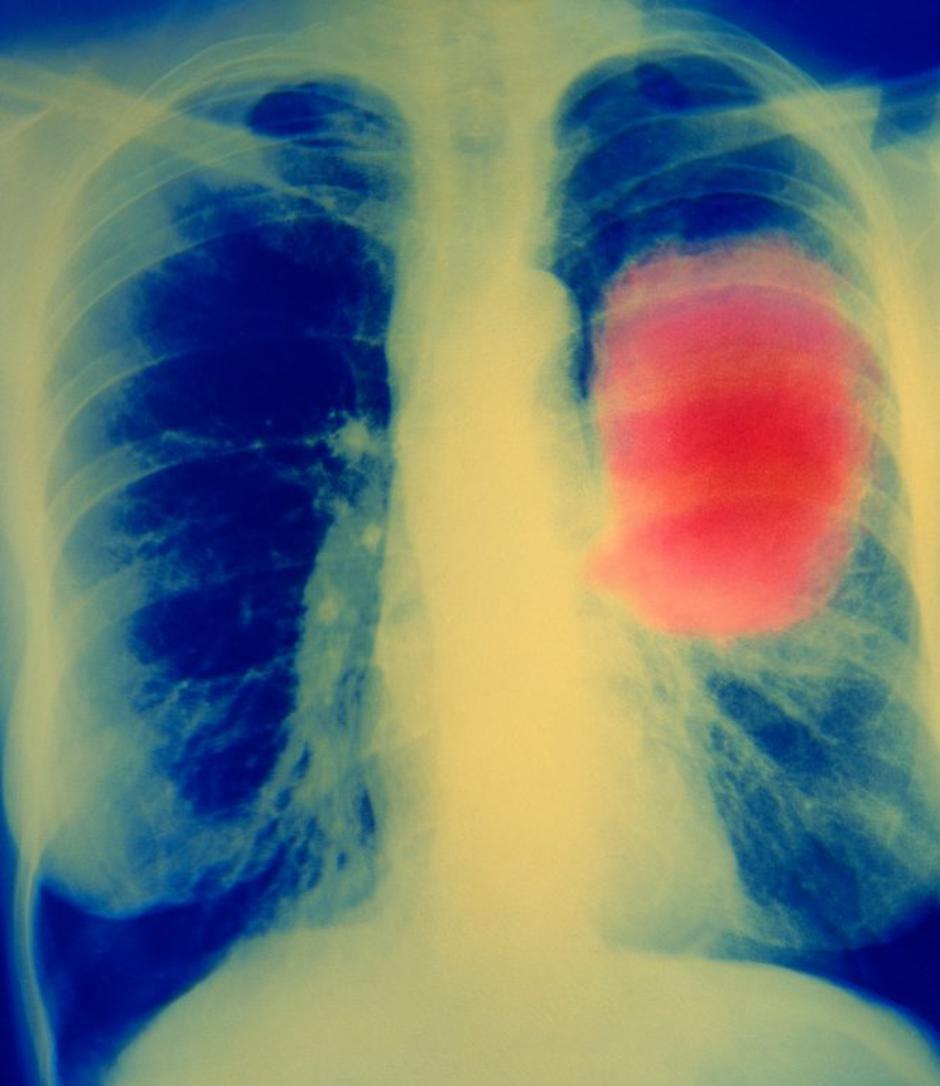

Rak na pljučih | Avtor: Profimedias Profimedias

Tveganje največje pri raku grla ter pljučnem raku

V veliki mednarodni prospektivni raziskavi EPIC (European Prospective Investigation into Cancer and Nutrition), v katero je bilo med leti 1992 in 2000 vključenih in več kot 10 let spremljanih več kot pol milijona Evropejcev, so ocenili, da lahko kajenju pripišemo 35 odstotkov vseh kadilskih rakov.  "Populacijsko pripisljivo tveganje je največje pri raku grla ter pljučnem raku (večje od 80 %), sledijo raki spodnjih sečil, ustnega in spodnjega žrela, požiralnika, ust, jeter in želodca s pripisljivim tveganjem med 20 in 50 %. Manj kot 20 % tveganja pa lahko pripišemo kajenju pri rakih nosnega žrela, debelega črevesa in danke, mucinoznih karcinomih jajčnika, rakih materničnega vratu, trebušne slinavke, mieloičnih levkemijah ter rakih nosu in nosnih sinusov," še piše v raziskavi za javnost.